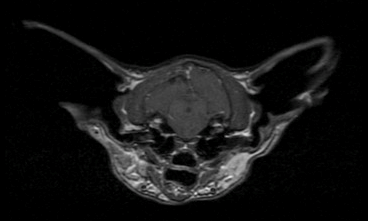

Disoriented cat with stumbling gait

MRI of the brain is shown. Which of the following best describes the condition shown?